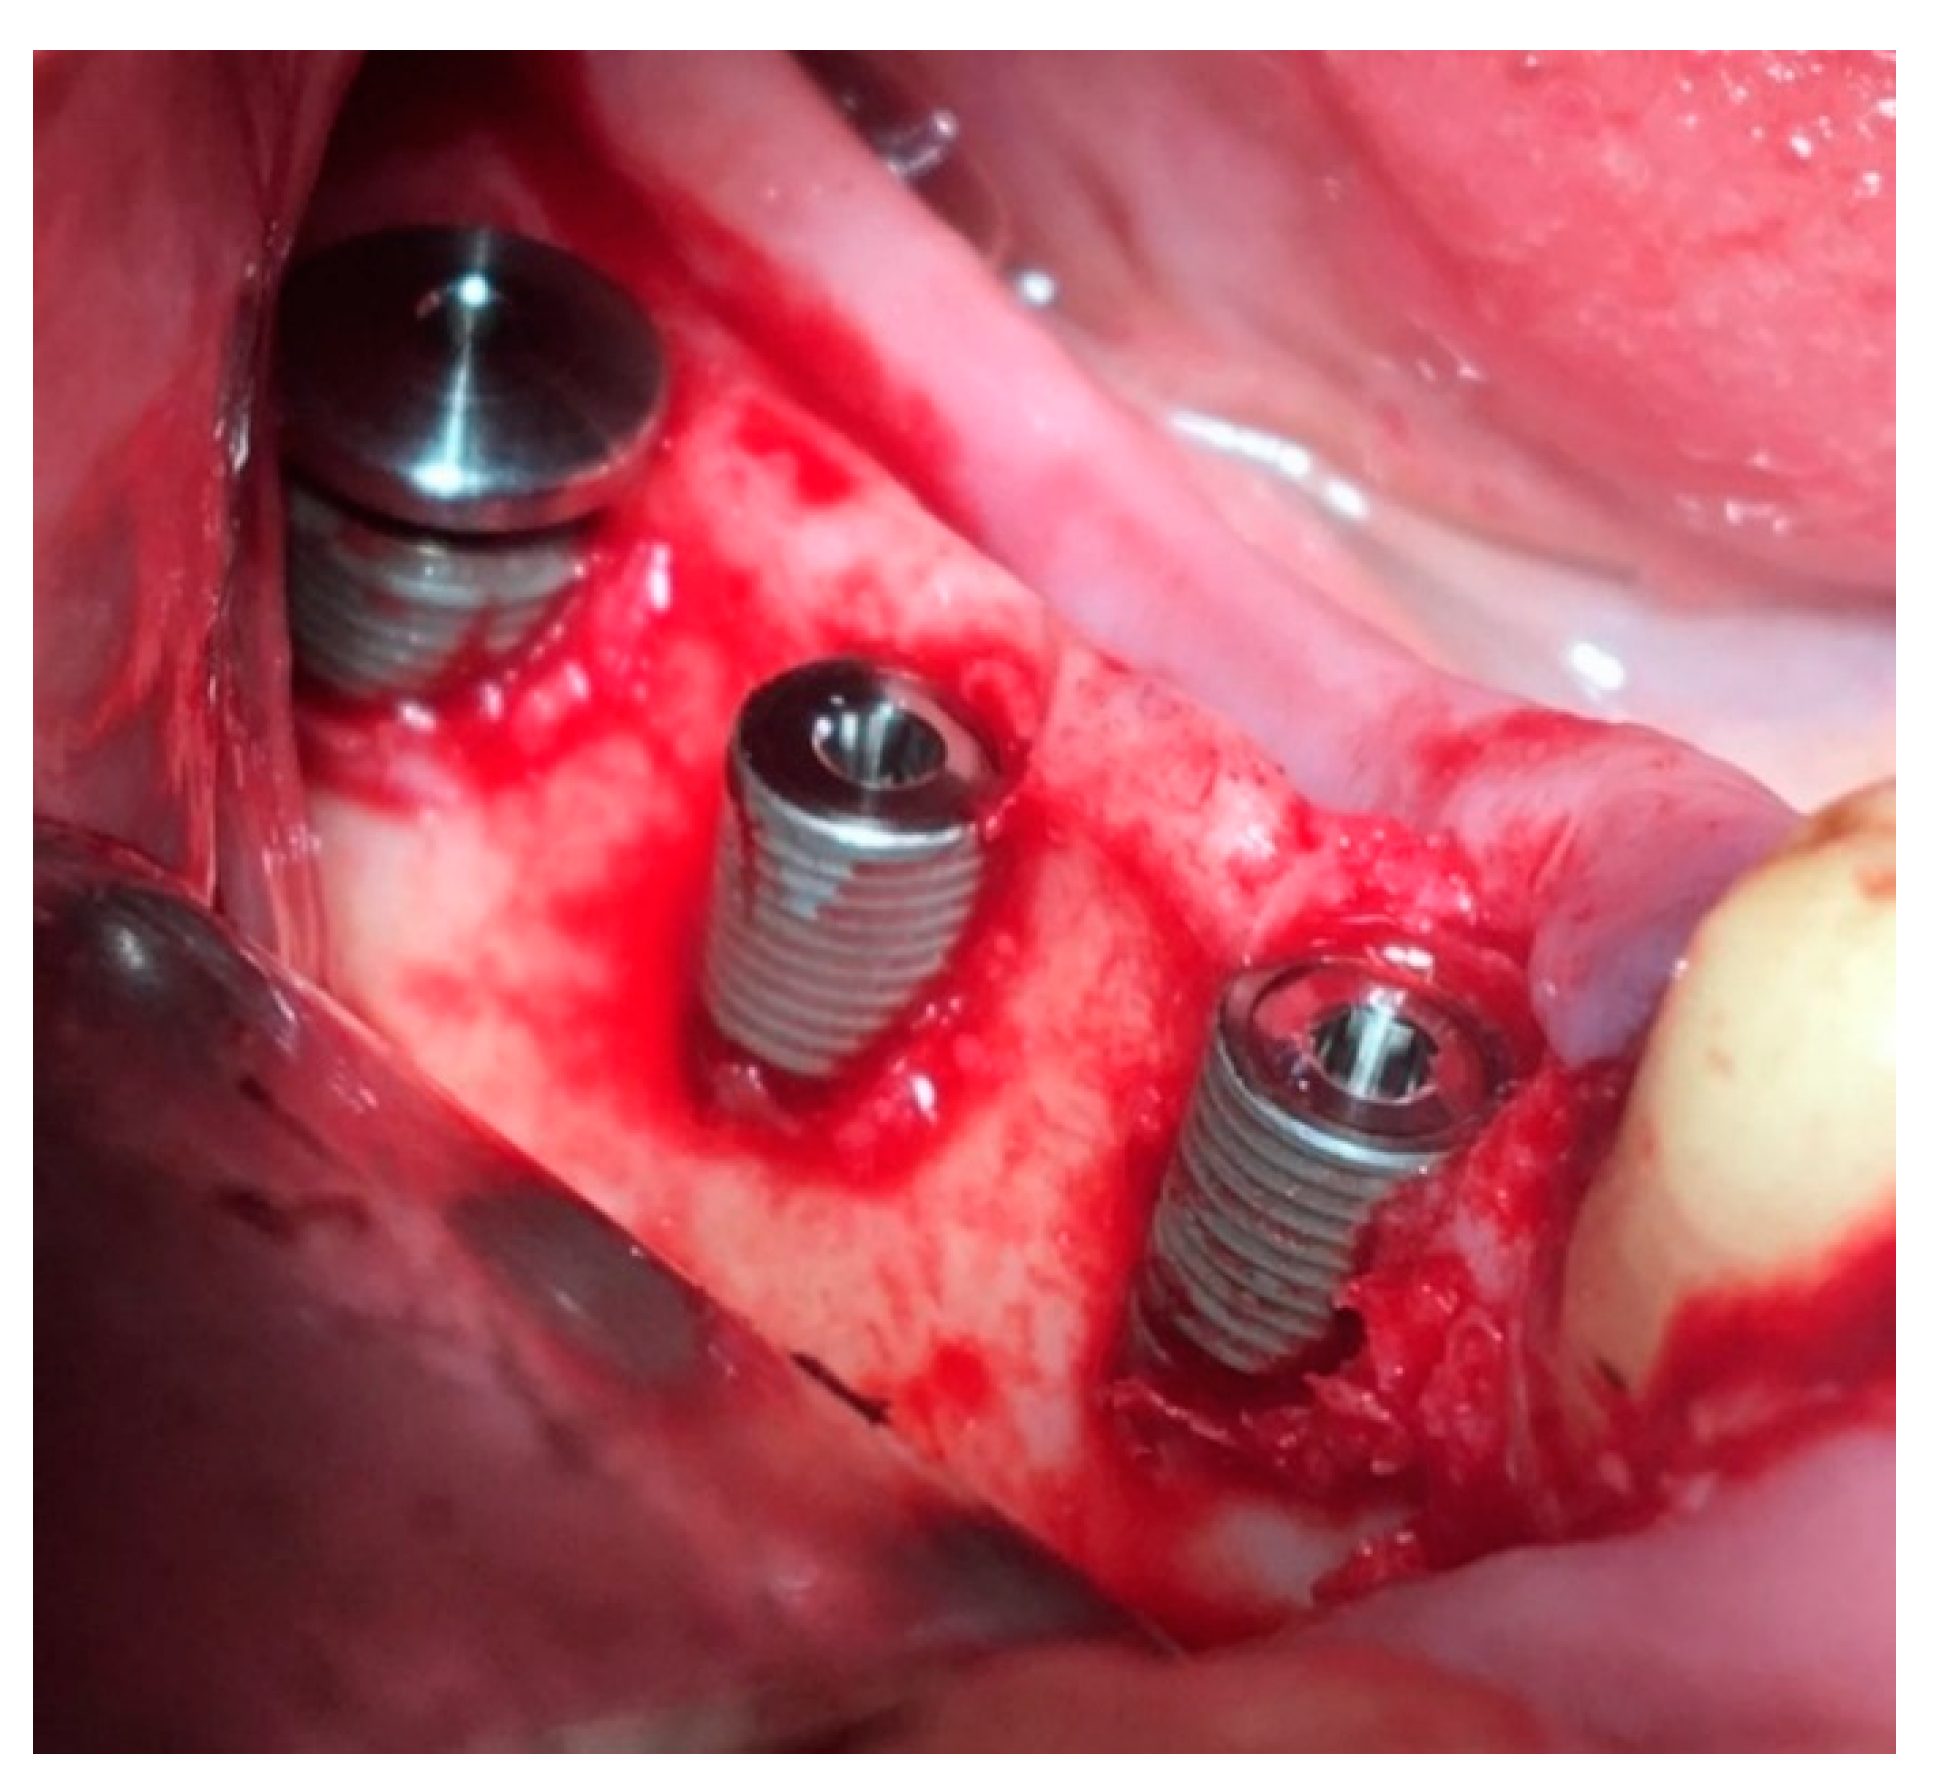

Surgical stage: dental implantation (Figure 8); horizontal and vertical JBD augmentation within the planned boundaries of the relief (Figure 9); the augmentate is covered with a membrane (Figure 10a); the wound is sutured in layers (Figure 10b).

Figure 8. Dental implants with plugs are installed, and ICX-Bone ring set consisting of a lock screw and cover screw is installed in the distal implant to fix the membrane.